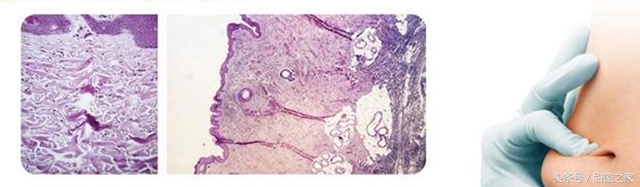

使用无针注射后皮下组织图片,皮下组织没有受到损失

液体软针,超细微孔,没有针头入侵皮肤,保持组织完整性